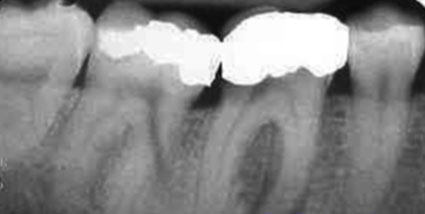

Hình: mô phỏng và x-quang của răng bị nhiễm trùng do sâu răng. Khi răng bị sâu và gây ra nhiễm trùng tủy, thần kinh và mạch máu trong tủy răng bị kích thích mạnh, làm tăng cảm giác đau và hạn chế hiệu quả của thuốc tê cũng như thuốc giảm đau, làm cho bạn cảm thấy “đau” nhiều hơn.

Hình ảnh và x-quang răng bị nhiễm trùng, tạo ổ nhiễm trùng ở hàm trên (abcess).